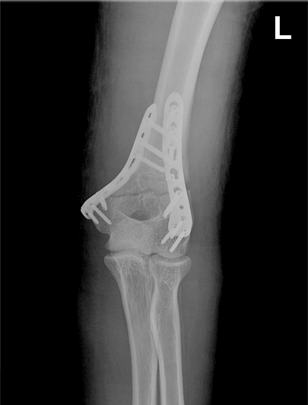

팔꿈치관절 골절의 종류 및 치료

과상부 골절, 요골두 골절, 척골 골절

과상부 어른 골절